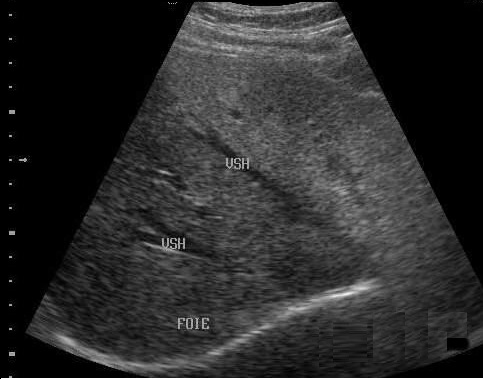

Image

echographique normale du foie . Le diapragme est en

vue tres net |

Image du foie normale : le foie est en

même echorich que la rein . Image echo

graphique du foie en coupe long sagitale . |